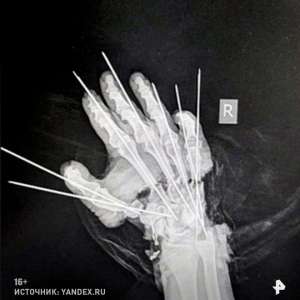

Можно ли восстановить руку, если она полностью отделена от тела? Посмотрите на это фото.

Специалисты из Санкт-Петербургского центра травматологии и ортопедии имени Вредена совершили невероятное. Сначала они совместили и зафиксировали костные фрагменты с помощью специальных металлических спиц.

Затем, используя микроскоп, они аккуратно соединили вены, артерии, сухожилия и нервы. Операция длилась целых семь часов!

Хотя последствия неосторожного обращения с деревообрабатывающим оборудованием, конечно, будут заметны, 28-летняя девушка сможет жить полноценной жизнью, имея обе руки!